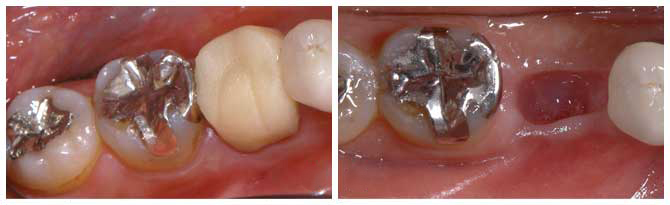

左下の一番奥歯が虫歯で抜歯となった30歳 女性

BEFORE

虫歯が大きく歯を残すことができずに抜歯となってしまいました。

レントゲンです。 向かって左端上の親知らずを、右下の奥に移植します。

AFTER

左の写真が親知らずを移植した直後のものです。 その後、根の治療をしクラウンを被せた状態の写真が右です。

移植後のレントゲンです。 BEFOREのレントゲンで空白だった部分におさまているのがわかると思います。